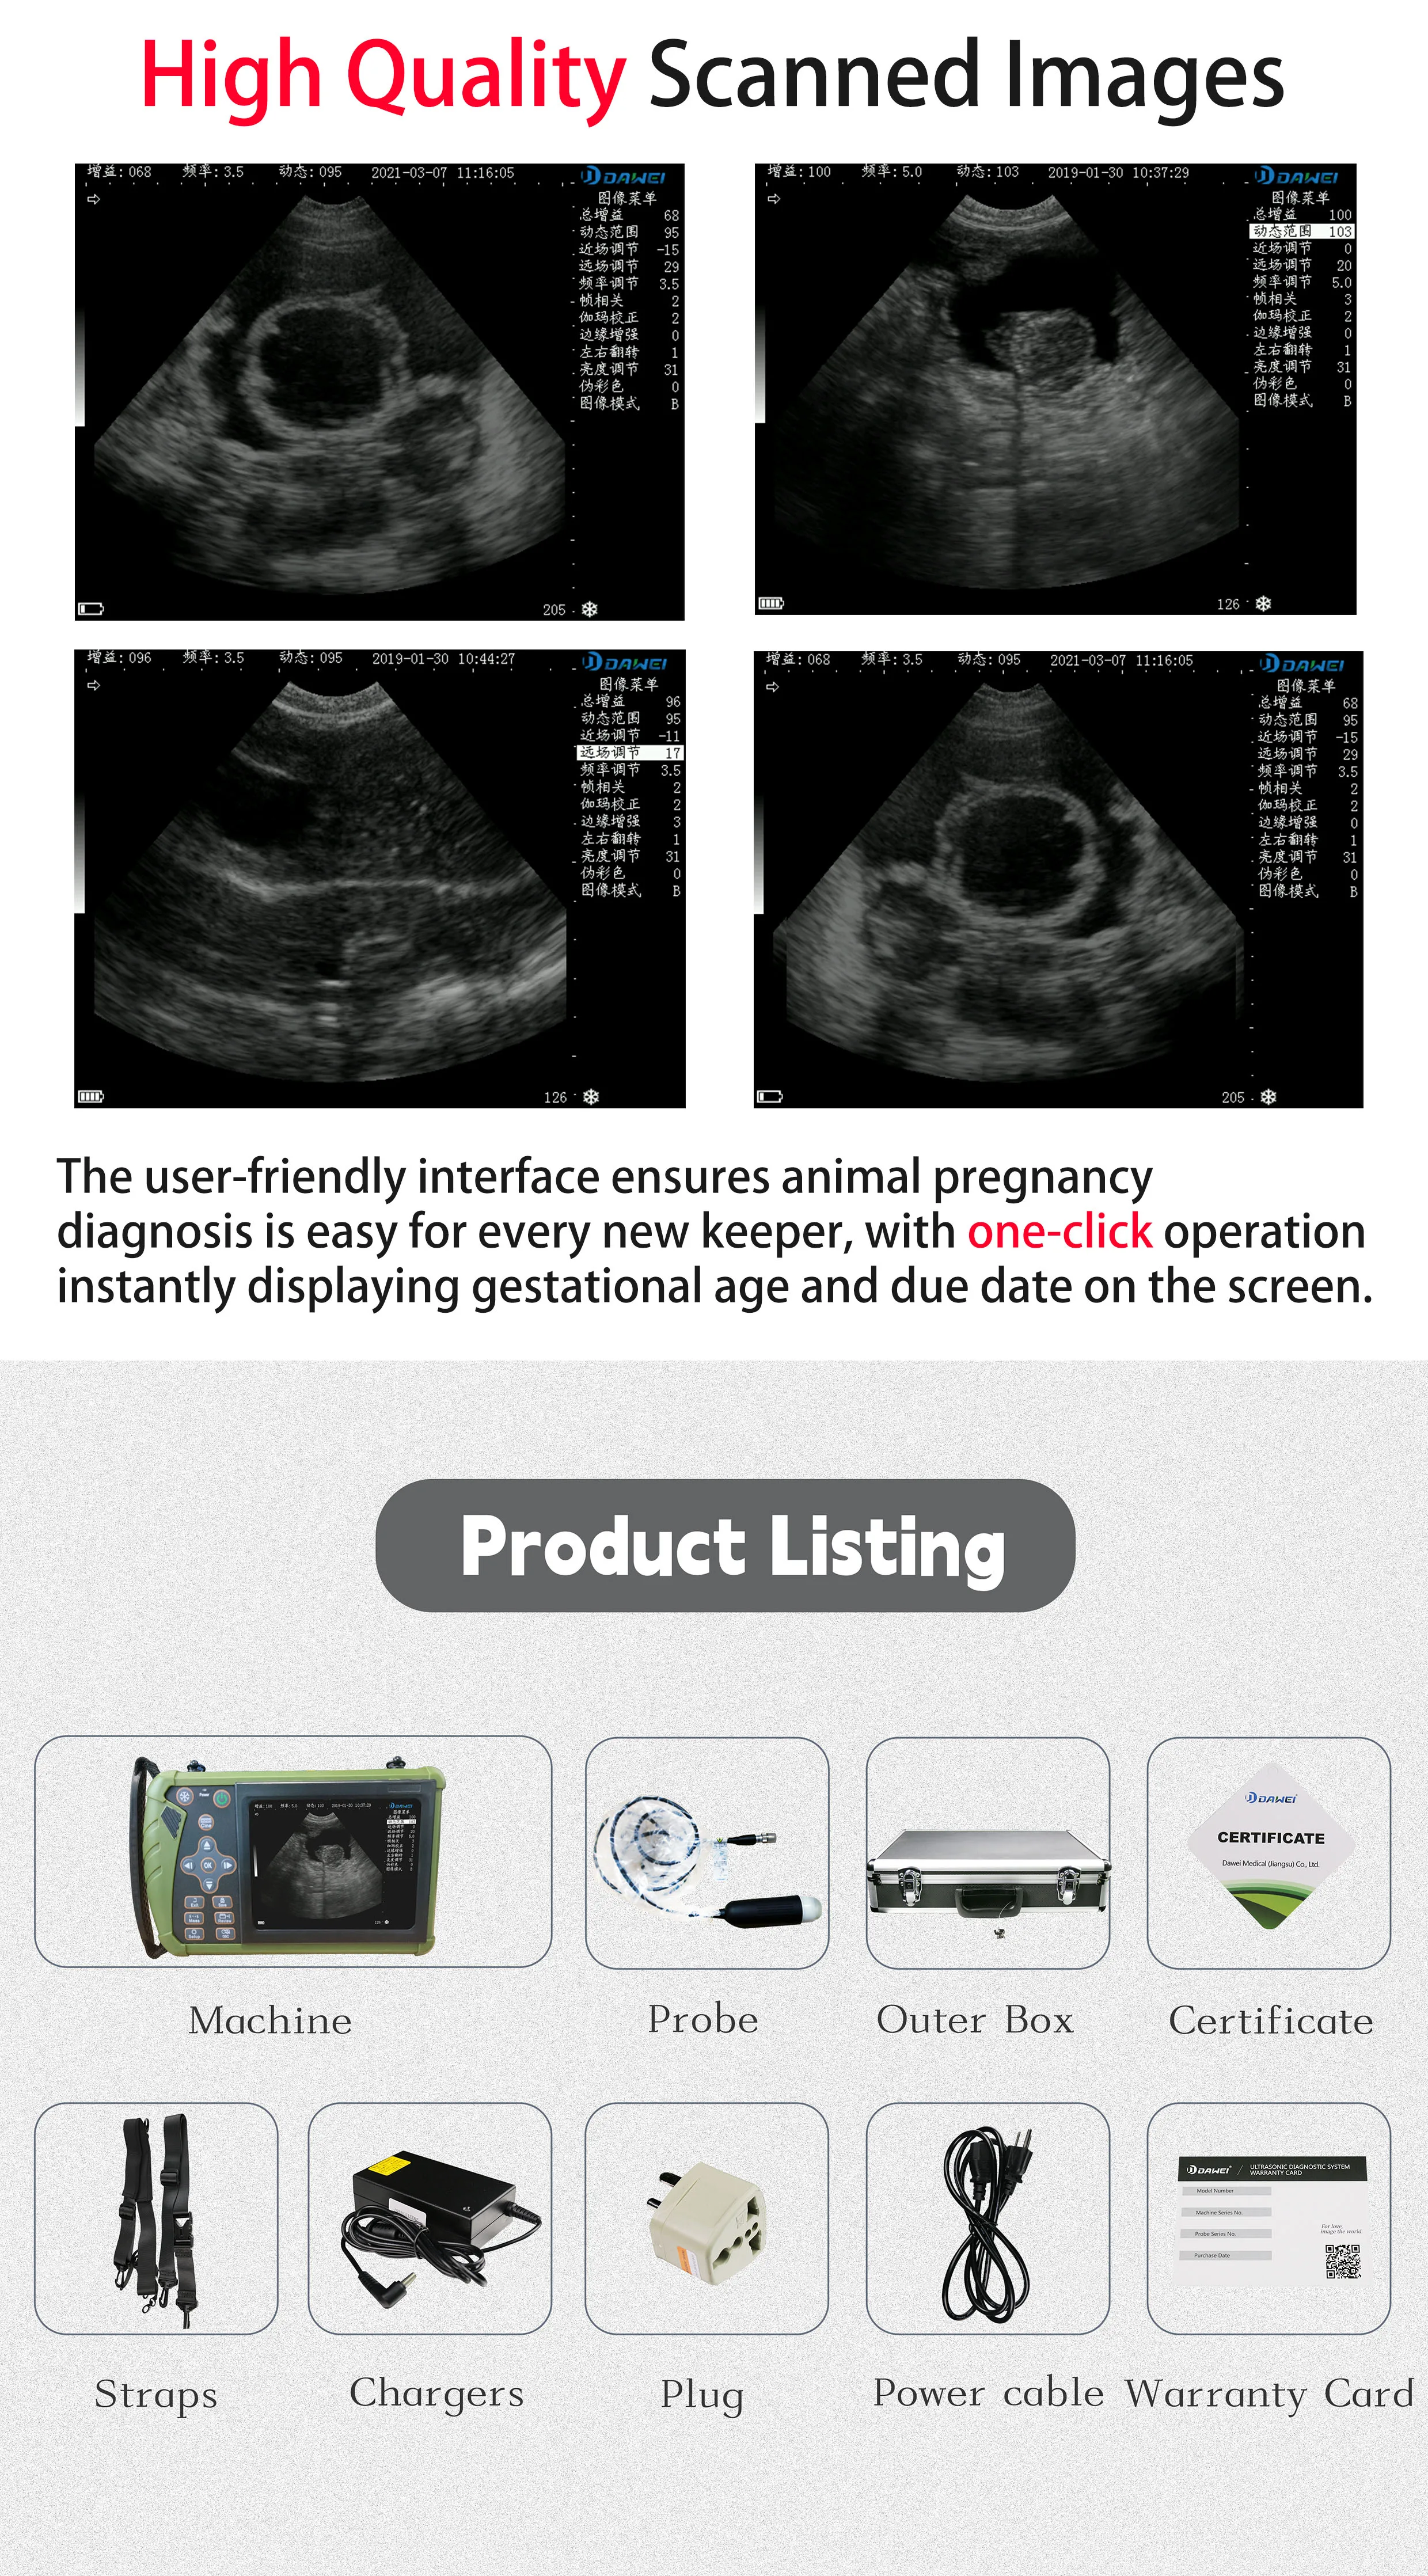

-Display mode: B,BM

-Image gray scale: 256 level

-Gain:30-105Db

-Measure: distance, area, obstetrics and other

GA(CRL),GA(BPD),GA(GS),GA(FL),GA(HC),GA(AC)

Standard Configuration:

-Main Host(probe) 1 Unit

-Internal Battery and charger 1 Set

-Non-slip lanyard